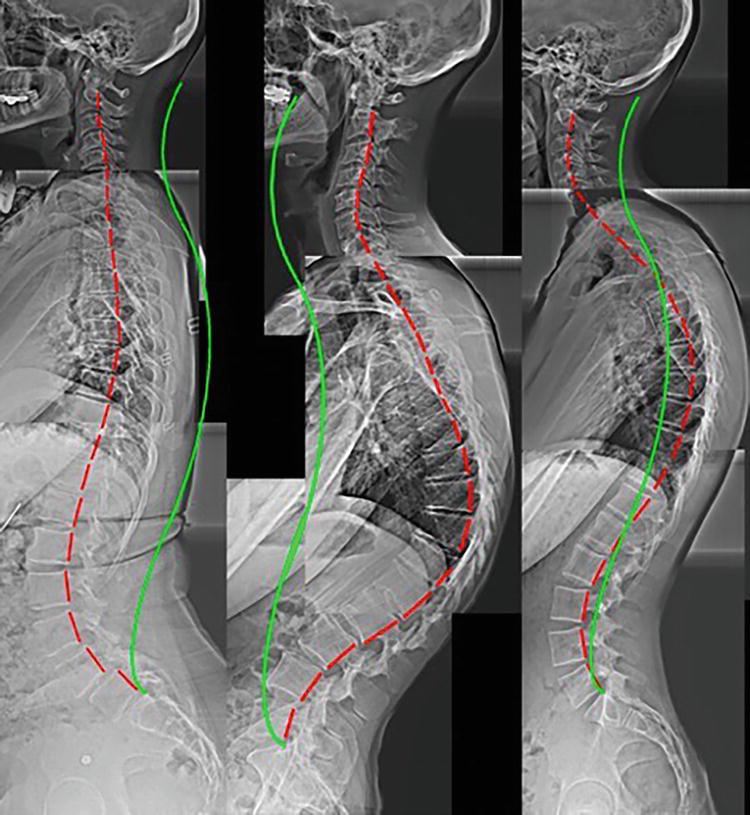

Various examples of structural abnormalities as seen on digital radiography (x-ray), green line represents normal alignment, red line represents patient's alignment

Various examples of structural abnormalities associated with forward head posture as seen on digital radiography (x-ray), green line represents normal alignment, red line represents patient's alignment.